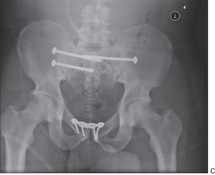

Fixation Open Book Pelvic Fracture Stock Photo Edit Now

Frontal X Ray Of Open Book Male Pelvis After Surgical Repair Of Stock Photo Alamy

Radiology Case Open Book Fracture Osteosynthesis